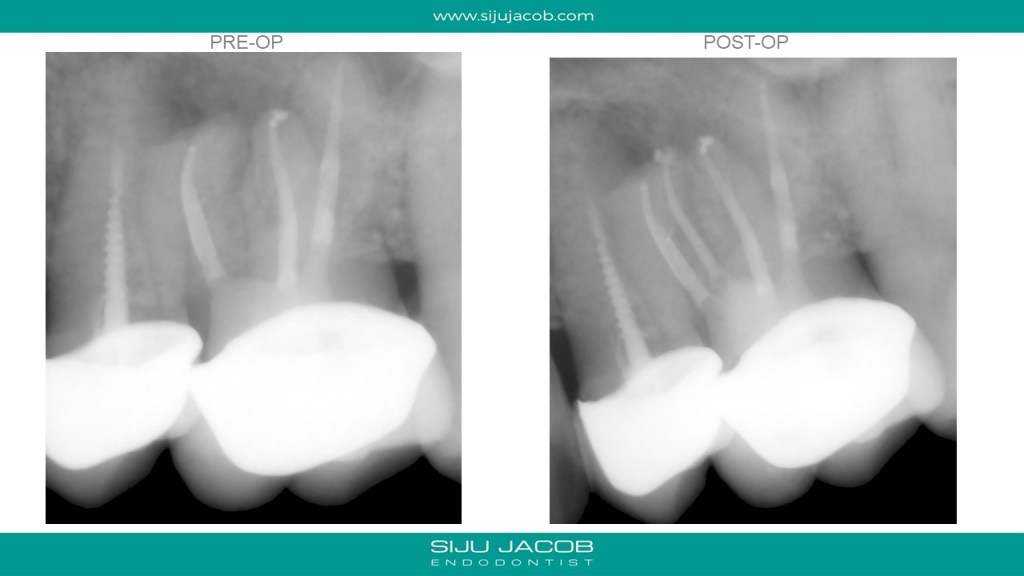

This is a Maxillary first molar treated several years ago and the patient came back with pain. CBCT shows missed MB2 with separate portal of exit. I located and treated only the MB2. Left the rest of the canals as they were.